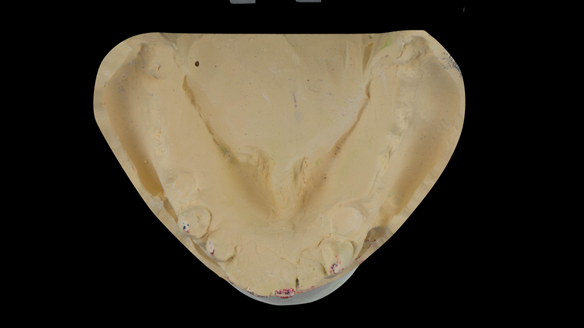

This newsletter describes in step by step detail the transition from acrylic based immediate dentures to metal based definitive dentures.

- Definitive dentures (Mk 2) – complete upper metal reinforced and lower cobalt chromium based partial of hygienic Scandinavian design to be made 9 - 12 months after extractions of all upper teeth and LR5 and LL4

The clinical situation and treatment process is shown in detail below with photographs.